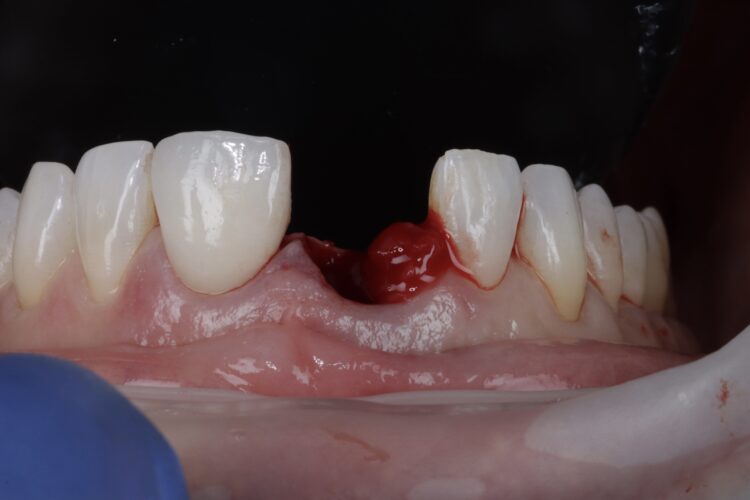

On the day of surgery, the post crown was removed, and the tooth sectioned to ease extraction while preserving the buccal plate. Forceps were used to deliver the fragments, with extensions to simplify pick-up (Hu-Friedy). The granulation tissue was removed using a Lucas curette.

Soft tissue regeneration

A free gingival graft was harvested from the palate, allowing enough tissue to reach between the base of each papilla and this was de-epithelialised to obtain the connective tissue. A thickness of 1mm is adequate, but in this instance, it was made intentionally thicker at the disto-buccal aspect to help plump up the papilla where bone loss was greater. The connective graft tissue was stabilised with three resorbable sutures placed, positioning the connective tissue graft 1mm below the free gingival margin.